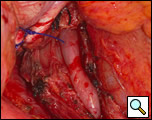

The surgical approach is a left posterolateral thoracotomy, entering the chest over the bed of the unresected 7th or 8th rib. On entering the thoracic cavity, the pulmonary ligament is divided and the lung is packed out of the way superiorly. The epiphrenic diverticulum is often found at the level of the inferior pulmonary vein. The pleura over the esophagus is divided allowing the esophagus to be gently mobilized. Penrose drains are used to encircle the esophagus superior and inferior to the diverticulum to facilitate the dissection (Figure 3). The diverticulum often arises to the right side necessitating rotation of the esophagus to clearly visualize the neck of the diverticulum. The diverticulum and its base are carefully dissected from the adjacent esophagus (Figure 4). Both vagus nerves are clearly identified and preserved during this maneuver. Once the diverticulum base is defined, a 40 Fr bougie is introduced across the gastroesophageal junction. This is performed under direct vision with the surgeon closely monitoring the safe passage of the bougie.